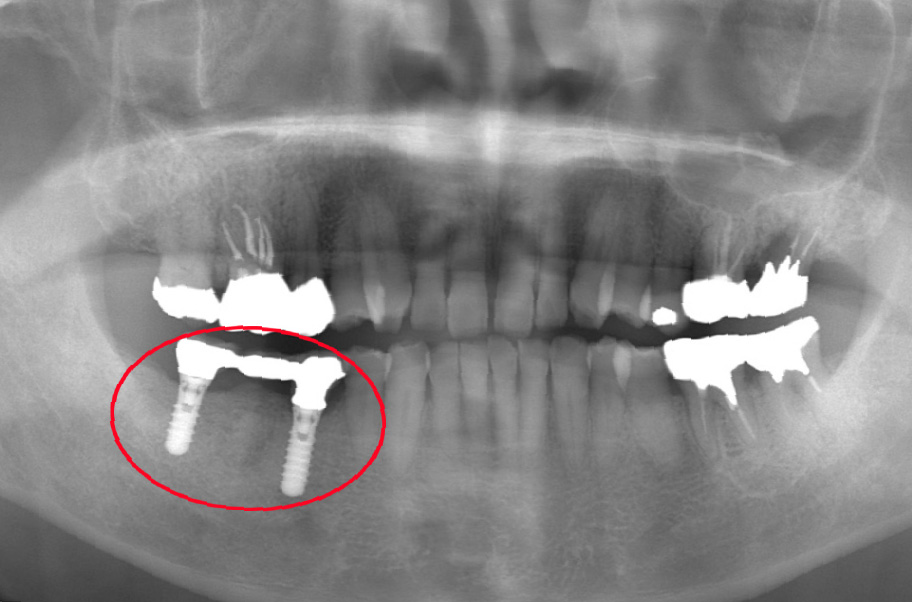

インプラント16年経過症例

80代になっても、ご自身の歯を一本も失わずに噛める喜び

【インプラント埋入直後】

2009年6月当時67歳

2009年6月当時

【16年後】

2025年4月83歳

患者様の概要

- 治療当時

- 67歳

- 現在

- 83歳(術後16年経過)

- お悩み

- 右下の歯が割れて抜歯になり、噛めない状態でした。

- 治療のポイント

- 歯を失った右下部分にインプラントを2本埋入し、連結した被せ物(ブリッジ)で噛み合わせを回復しました。

治療から16年が経過し、患者様は83歳になられましたが、インプラントの状態は非常に良好です。

何より素晴らしいのは、「インプラントがしっかりと噛む力を支えてくれたおかげで、 他のご自身の歯への負担が減り、この16年間でさらに歯を失うことがなかった」という点です。

3~4ヶ月ごとの定期的なメンテナンス(パウダーによるクリーニング等)にもしっかりに通っていただいた結果、 現在もしっかりとご自身の歯で食事を楽しんでおられ、全身の健康も素晴らしい状態です。

治療データ

- 治療期間・回数

- 約5ヶ月(通院12回)

- 費用(治療当時)

- 総額 88万円(税込)

内訳:インプラント手術 44万円(インプラント2本埋入)、被せ物 44万円 - リスク・副作用